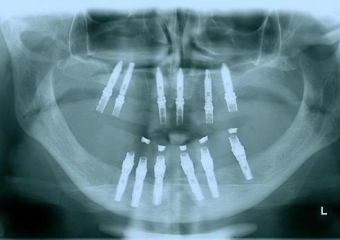

Imagem implantes inferiores em 2006 - Clínica Cliniface

Imagem implantes inferiores em 2006